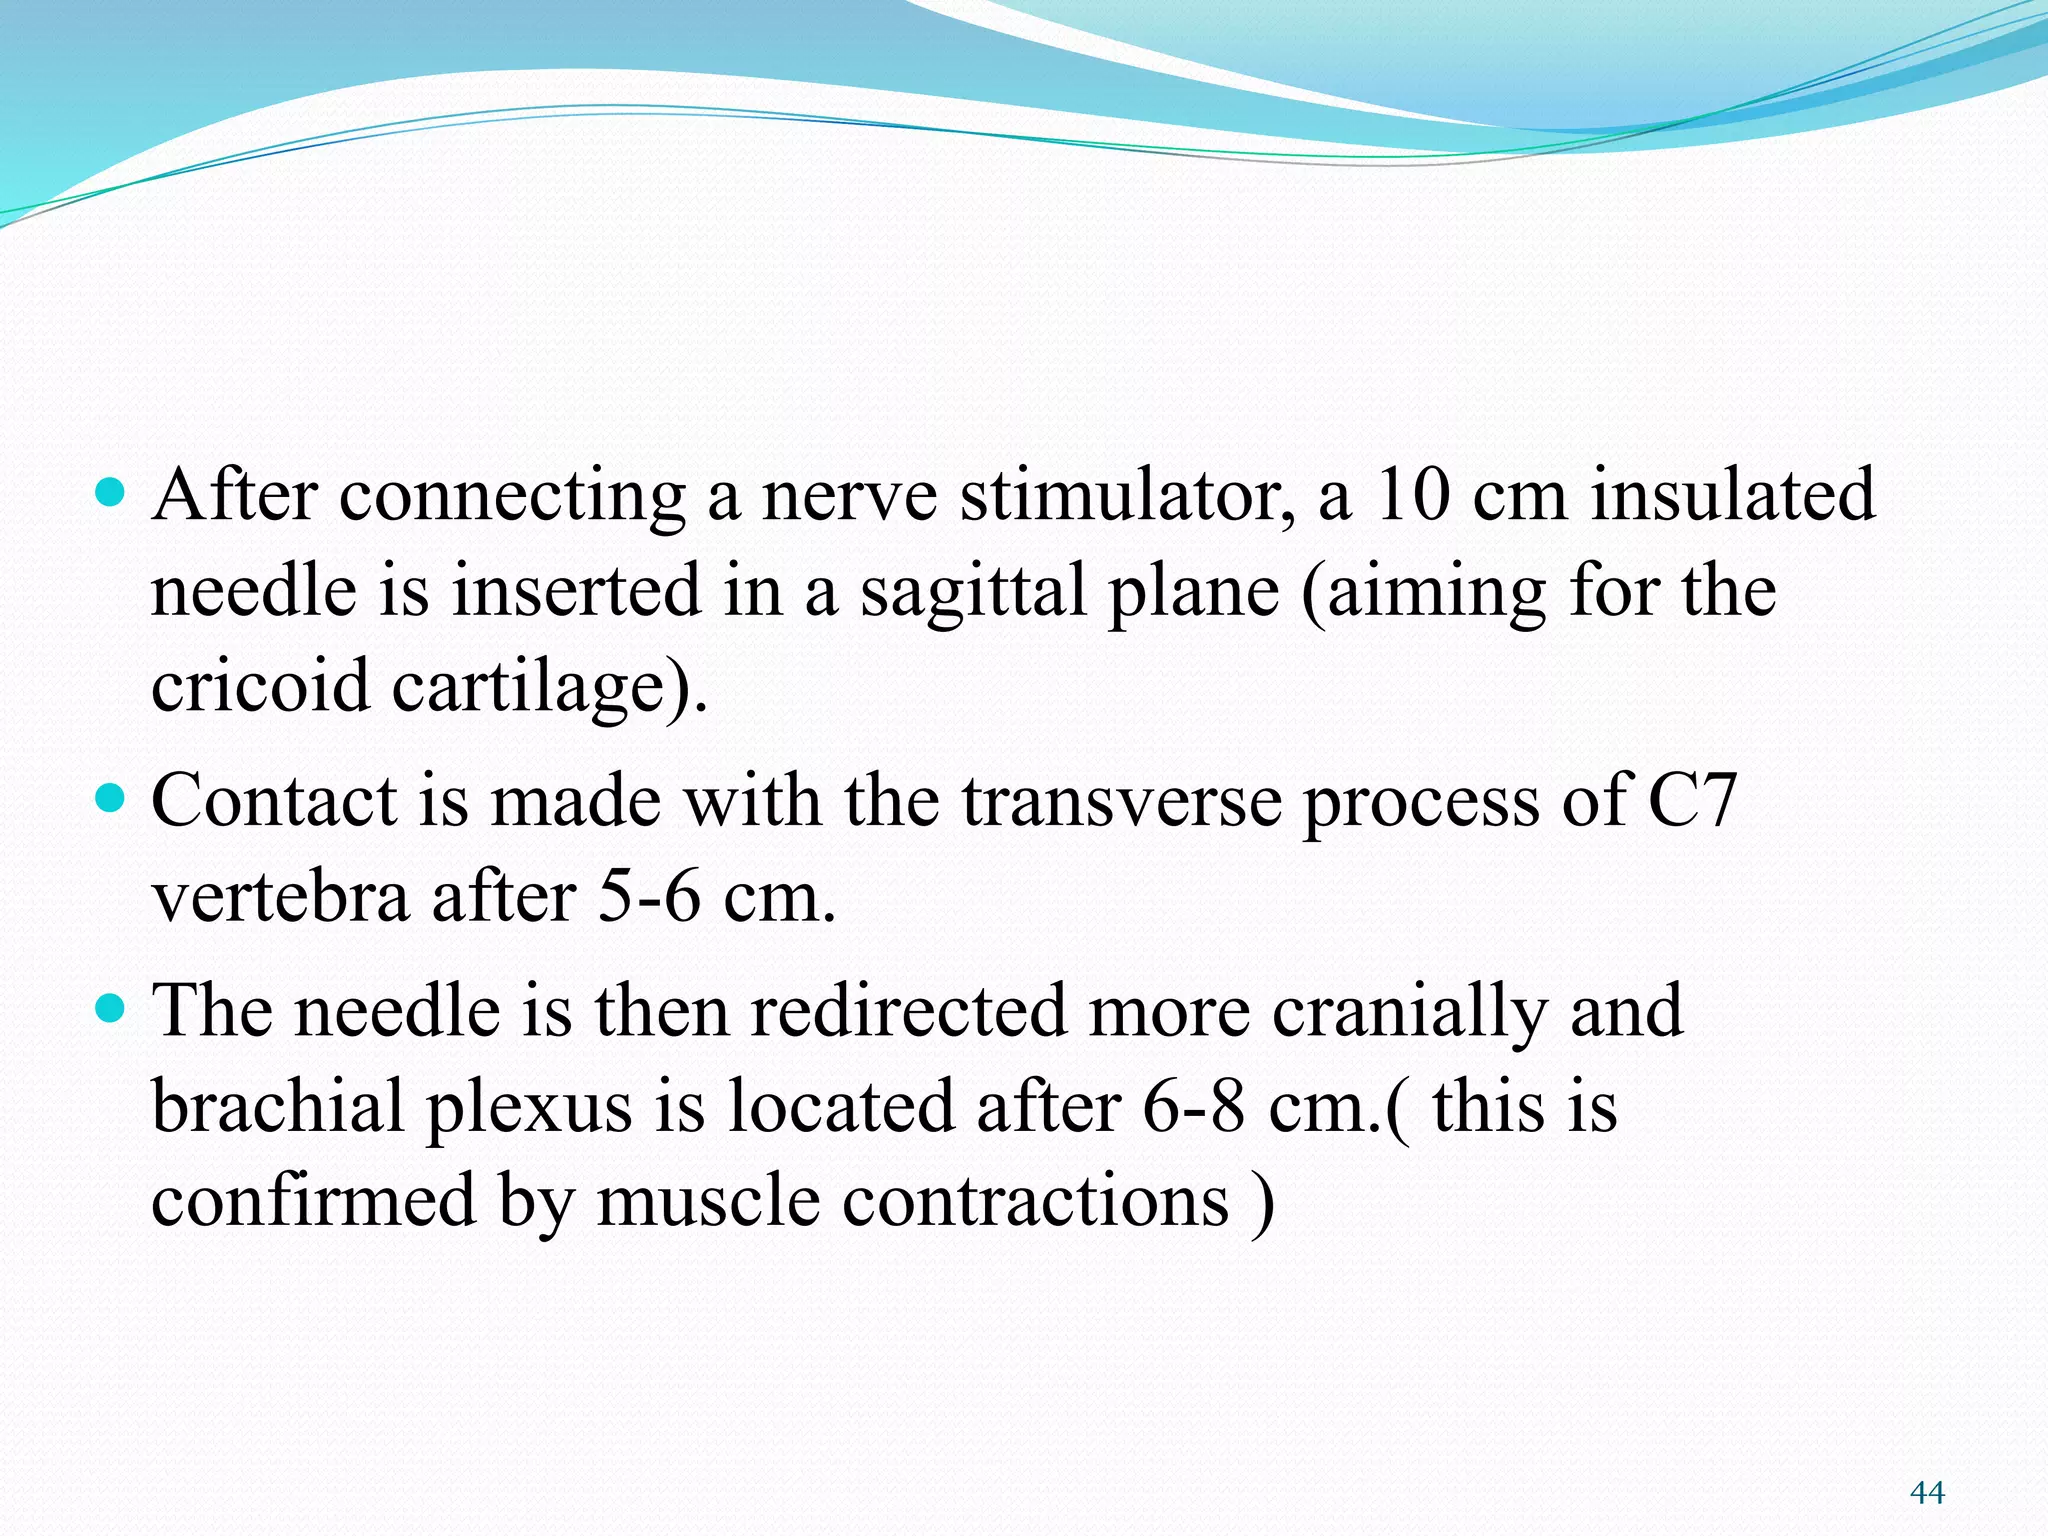

This document provides an overview of brachial plexus anatomy and techniques for brachial plexus nerve blocks. It begins with a description of the brachial plexus formation from cervical and thoracic nerve roots and its branching pattern. Four main approaches for brachial plexus nerve blocks are described: interscalene, supraclavicular, infraclavicular, and axillary. Details are provided on the anatomy and techniques for performing interscalene and supraclavicular brachial plexus blocks. Ultrasound guidance is discussed as an advancement which allows real-time visualization of needle and nerve. Complications are also summarized.